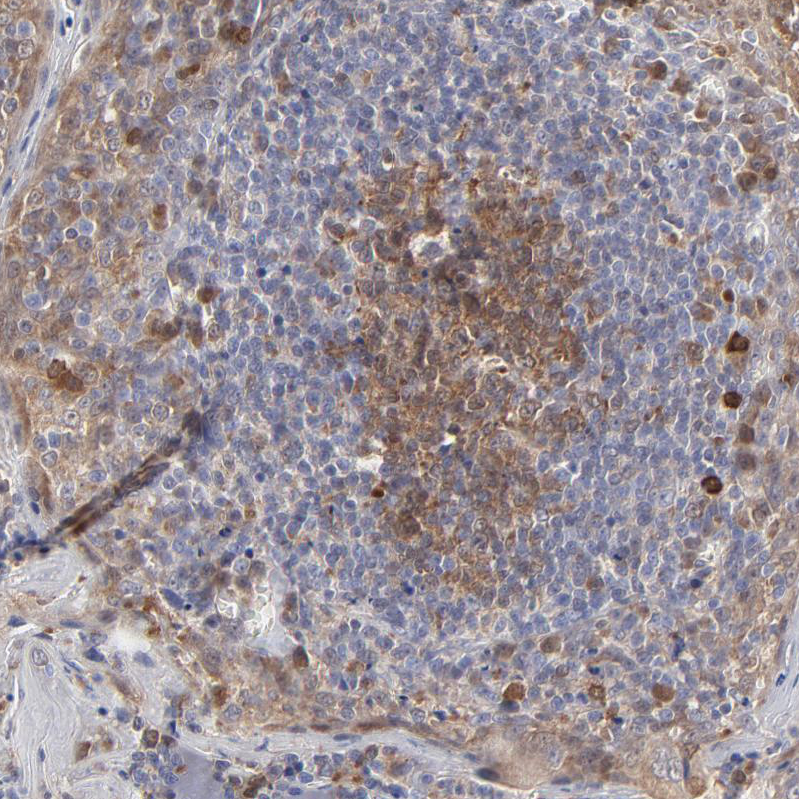

Immunohistochemistry analysis in human lymph node and skeletal muscle tissues using HPA002643 antibody. Corresponding CASP3 RNA-seq data are presented for the same tissues.